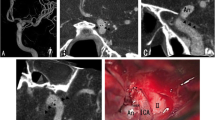

Three segments of EC/IC bypass were visualized and rated separately: the extracranial STA segment (ECS), the trepanation segment with passage across craniotomy (TS), and the intracranial segment with STA-MCA anastomosis (ICS) (Fig. 1a). To assess vessel integrity and patency after image processing with the DEBR algorithm (Fig. 1b), visualization of bypass segments was rated on DEBR-CTA images and unsubtracted CTA images (0=not visible, 1=poorly visible/significant stenosis, 2=fair contrast/focal minor stenosis, 3=good contrast/no significant stenosis, 4=excellent contrast, no stenosis). To assess diagnostic accuracy of rated bypass visualization, scores of CTA images (with and without DE bone removal) were compared with scores of gold standard DSA (Fig. 1c; bypass visualization and function based on the extend of intracranial MCA filling over the bypass; 0 none, 1 sparse, 2 ante-/retrograde filling of MCA branches, 3 entire MCA territory, 4 +ACA territory).

Angiography of EC/IC bypass (CTA, DEBR-CTA, DSA). a Inverted thick slap MIP of CTA source images without bone removal. The three segments of the EC/IC bypass that were rated separately are depicted: the extracranial STA segment (ECS); the trepanation segment (TS); the intracranial segment with STA-MCA anastomosis (ICS). b After processing of CTA source images using the DE bone removal algorithm, all bone is removed allowing complete visualization of bypass; the inverted thick slap MIP provides a DSA-like image. c Gold standard DSA for postsurgical evaluation of bypass patency

In 6 out of 24 cases, bypass close to bone in source images of DEBR-CTA was erroneously misclassified as bone so that affected voxels were set to −1024 HU by the DEBR algorithm (Fig. 2). Thus, in these cases the DEBR algorithm had a negative effect on vessel integrity with an apparent discontinuity of vessel in source images mimicking focal stenosis with “pseudo-gaps” in MIP images (Fig. 3). Without a priori knowledge of erroneous misclassification, these “pseudo-gaps” were significant as they affected rating for visualization of bypass segment TS compared to gold standard DSA.

Source images of CTA and DEBR-CTA. a The CTA source image without bone removal shows EC/IC bypass adjacent to bone (closed arrow) when crossing the site of craniotomy (TS segment). b Focal erroneous misclassification of bypass close to bone (open arrow) in the corresponding CTA source image with DE bone removal

“Pseudo-lesion” in DEBR-CTA. “Pseudo-lesion” in maximum intensity projection of CTA with dual energy bone removal (b; open arrow): apparent focal bypass stenosis due to misclassification of vessel close to bone was verified as patent normal appearing bypass in DSA and CTA source images without bone removal (a, b; closed arrows)